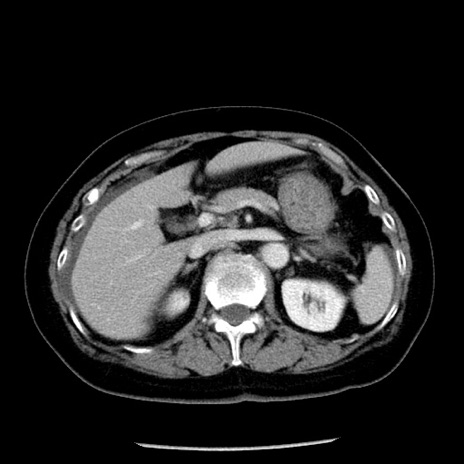

症例13(横断像)

【症例】70歳代女性

【主訴】腹痛、嘔吐

【現病歴】15時間程前(昨晩)より腹痛あり。今朝になっても症状の改善なく、嘔吐あり。腹痛も増悪あり、救急外来受診。

【既往歴】子宮癌全摘術後

【身体所見】意識清明、BP 121/72mmHg、P 74bpm、SpO2 100%(RA)、腹部:平坦・軟、腸雑音ほぼ聴取せず。下腹部・心窩部・臍左上に圧痛あり。反跳痛なし。

【データ】WBC 10600、CRP 0.15